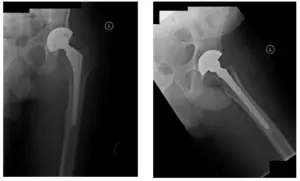

Left THA Revision performed in 2011.

X-Ray of Pelvis during operation